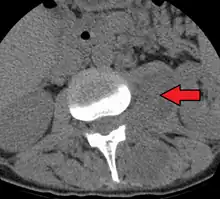

Psoas abscess is a collection of pus in the iliopsoas muscle compartment.[1][2] It can be classified into primary psoas abscess (caused by hematogenous or lymphatic spread of a pathogen) and secondary psoas abscess (resulting from contiguous spread from an adjacent infectious focus).[2]

Psoas abscess may be caused by lumbar tuberculosis. Owing to the proximal attachments of the iliopsoas, such an abscess may drain inferiorly into the upper medial thigh and present as a swelling in the region. The sheath of the muscle arises from the lumbar vertebrae and the intervertebral discs between the vertebrae. The disc is more susceptible to infection, from tuberculosis and Salmonella discitis. The infection can spread into the psoas muscle sheath.[3]

Paraspinal abscess in the psoas muscle